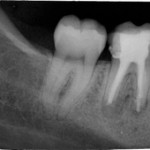

Nach mehreren medikamentösen Einlagen (1x Ledermix, anschließend 4x CHKM, Probe-WF mit Ca(OH)2) konnte der Zahn Ende Januar 2008 erneut wurzelgefüllt werden (laterale Kondensation mit Guttapercha und Endomethasone N). Zu diesem Zeitpunkt zeigte sich bereits eine deutliche Verknöcherung des Defektes als Zeichen einer Heilung der apikalen Ostitis.